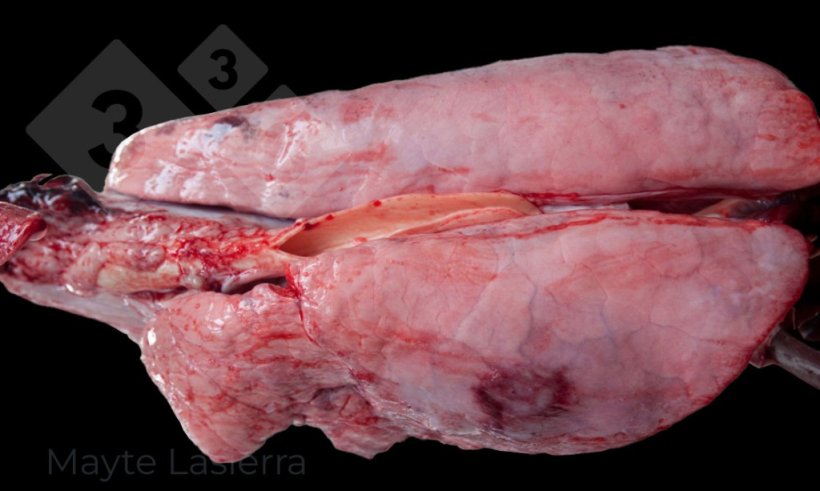

Dans les poumons examinés à l'abattoir, les lésions les plus fréquemment observées sont les bronchopneumonies de localisation crânio-ventrale et les pleurésies.

Les bronchopneumonies crânio-ventrales sont principalement associées à la pneumonie enzootique. Ces lésions se présentent sous forme de zones de consolidation, dures à la palpation, de couleur grise à violette selon l'ancienneté de la lésion et les complications bactériennes secondaires.

Processus de bronchopneumonie

Les pleurésies sont fréquentes et sont des lésions qui touchent la région dorso-caudale du poumon, principalement associées aux formes subaiguës ou chroniques de la pleuropneumonie porcine (APP). Elles se manifestent sous forme de zones blanchâtres sur la plèvre viscérale des lobes diaphragmatiques, qui correspondent à des dépôts de fibrine.